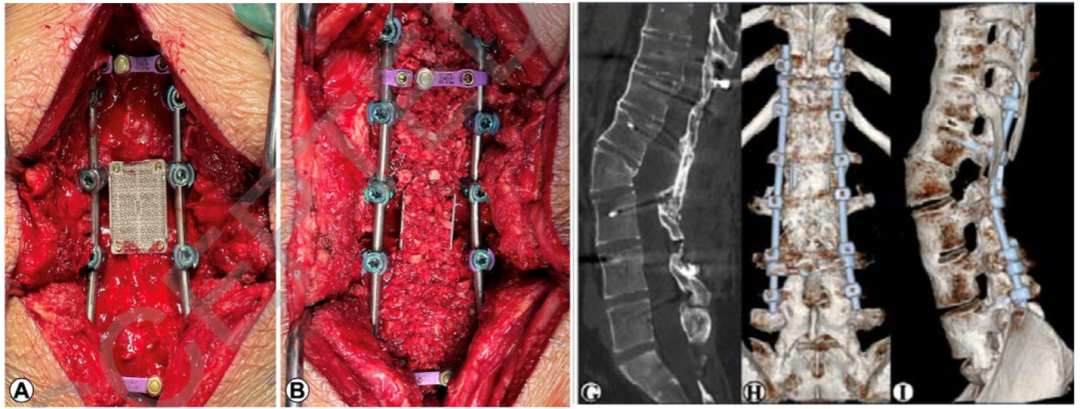

针对严重的角状脊柱侧后凸畸形 ,Zhou等对比了保留后方韧带复合体(PLC)的改良PVCR与传统PVCR两种手术策略 。结果显示,改良PVCR在畸形矫正方面表现更佳(局灶性后凸矫正率显著更高:62.26% vs 51.46%) ,且神经并发症发生率显著降低。这提示保留PLC有助于在截骨闭合过程中维持脊柱稳定性、控制截骨端位移并防止过度短缩,从而使改良PVCR成为比传统技术更安全、矫形效果更优的选择 [25]。